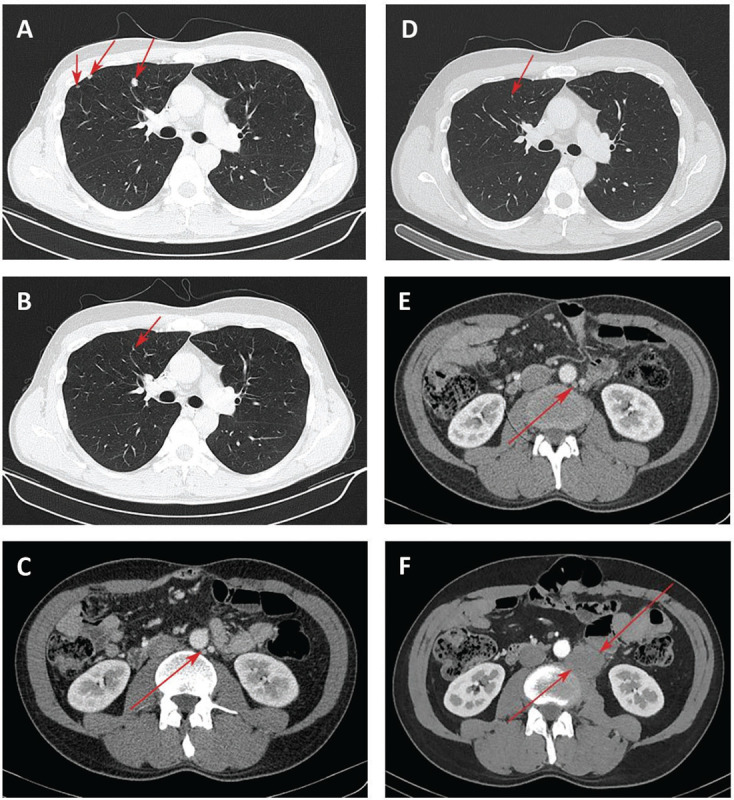

Immunotherapy has become an integral part of a comprehensive treatment approach to metastatic colorectal cancer (mCRC). Nivolumab (Opdivo) is a human immunoglobulin G4 monoclonal antibody that blocks the interaction between the programmed cell death 1 (PD-1) receptor and its ligands 1/2 (PD-L1/PD-L2), leading to inhibition of T-cell proliferation, cytokine secretion, and enhanced immune response. The US Food and Drug Administration (FDA) has approved this drug for use in high microsatellite instability (MSI-high)/deficiencies in mismatch repair (dMMR) advanced CRC patients. However, its efficacy is extremely limited in microsatellite stability (MSS)/mismatch repair proficient (pMMR) patients. We report a case of a 42-year-old man diagnosed with MSS/pMMR mCRC who has achieved a durable response to nivolumab after a progression under chemotherapy with antiangiogenic treatment. We observed for the first time an atypical response after 8 months of nivolumab treatment, with the regression of previous primary pulmonary lesions and the presence of new para-aortic lymph node lesions. This report demonstrates that a subset of pretreated mCRC patients with the MSS/pMMR phenotype may benefit from nivolumab and these patients need more attention.